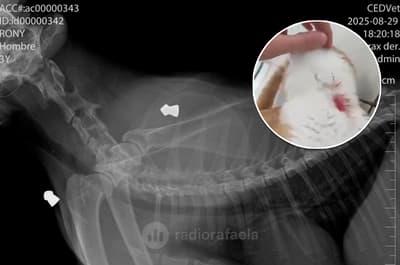

Maltrato animal: hirieron a un perro con una flecha que le quedó incrustada en la zona dorsal

<![CDATA[<figure><img src="https://cdnartic.ar/YAS6ILcpZeykcxi1t-6SkXR-IVs=/800x0/filters:no_upscale():format(webp):quality(40)/https://radiorafaelacdn.eleco.com.ar/media/2025/12/maltrato_animal_hirieron_a_un_perro_con_una_flecha_que_le_quedo_incrustada_en_la_zona_dorsal.webp" class="type:primaryImage" /></figure><p>Un caso de maltrato animal generó conmoción este miércoles por la mañana en San Francisco, cuando un perro fue encontrado con una flecha incrustada en la zona dorsal derecha del abdomen. La situación se conoció a partir de una denuncia realizada a la línea 103, que alertó sobre el animal herido en la intersección de calle Güemes y el camino interprovincial.</p><p>Al recibir el aviso, la Guardia Local acudió al lugar y tomó contacto con el dueño del perro, quien indicó que la lesión habría ocurrido durante la noche anterior. Los agentes registraron imágenes del estado del animal y elevaron la información al Centro de Atención Ciudadana, que rápidamente notificó a la coordinadora de Sanidad Animal, Mariana Ghigo.</p><p>&nbsp;</p><p>&nbsp;</p><p>Siguiendo sus indicaciones, se dispuso el traslado urgente del perro a la Unidad Móvil de Castraciones, ubicada en Almafuerte 1516, en el Centro Vecinal de barrio José Hernández.</p><p>&nbsp;</p>Atención veterinaria y recuperación<p>En la unidad móvil, el animal fue recibido por el veterinario Lucas Peralta y por Dahiana Broglia, quienes realizaron las curaciones necesarias para estabilizarlo y controlar la lesión provocada por la flecha. Tras la asistencia y una vez que se verificó su evolución favorable, el perro fue retirado por sus dueños.</p><p>&nbsp;</p><p>&nbsp;</p>]]>